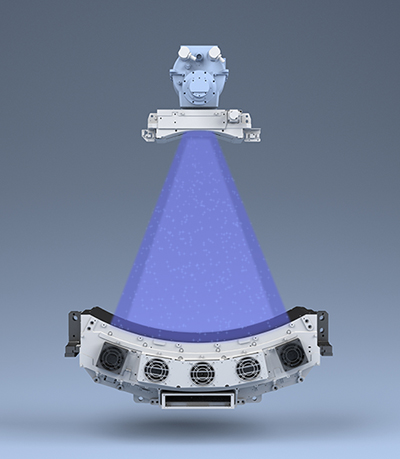

- 0,5 мм × 80 ряд детекторов PUREViSION4;

Технология PURE ViSION Optics фильтрует низкоэнергетические фотоны, обеспечивая более однородный спектр, который улучшает качество изображения и снижает дозу облучения пациентов.